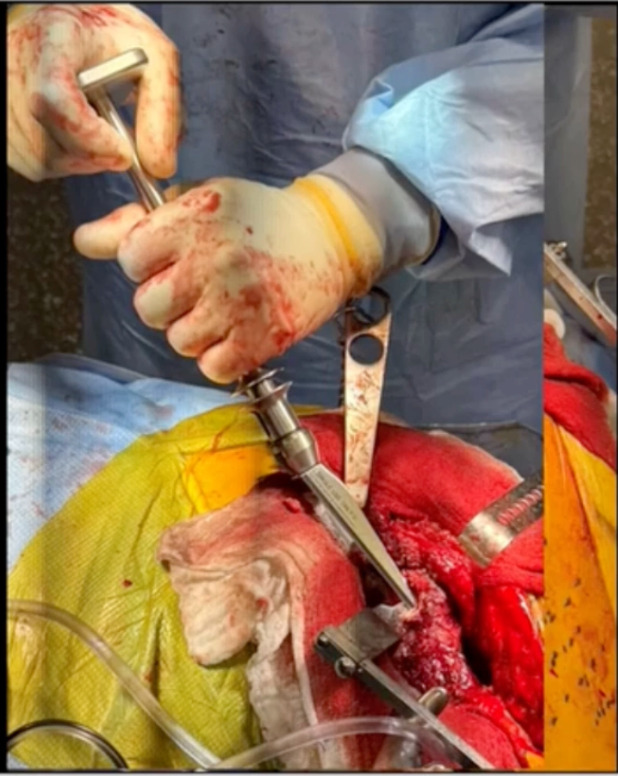

This is one around the calcar area. The idea is to use what you can to make it happen. (Figure 8)

Cup osteotomes. This is an example of just using our Slap Hammer extractor. (Figure 9)

We’re able to successfully extract the cup. He did have really poor proximal bone around that shoulder. He ended up having a fracture there as well. But got the cup out, did all the things here important. But the idea is that because he did have an infection, you’ve got to do an aggressive debridement. That’s one thing I was taught. It’s almost an oncologic debridement. I do use some products that are available to us in the US. Bactisure antiseptic lavage, which is a kind of a flamethrower not dissimilar to Daikin’s, but probably less harmful and then another product called Xperience antiseptic lavage. But the idea, as Cerny emphasized to me, was a double setup. (Figure 10)